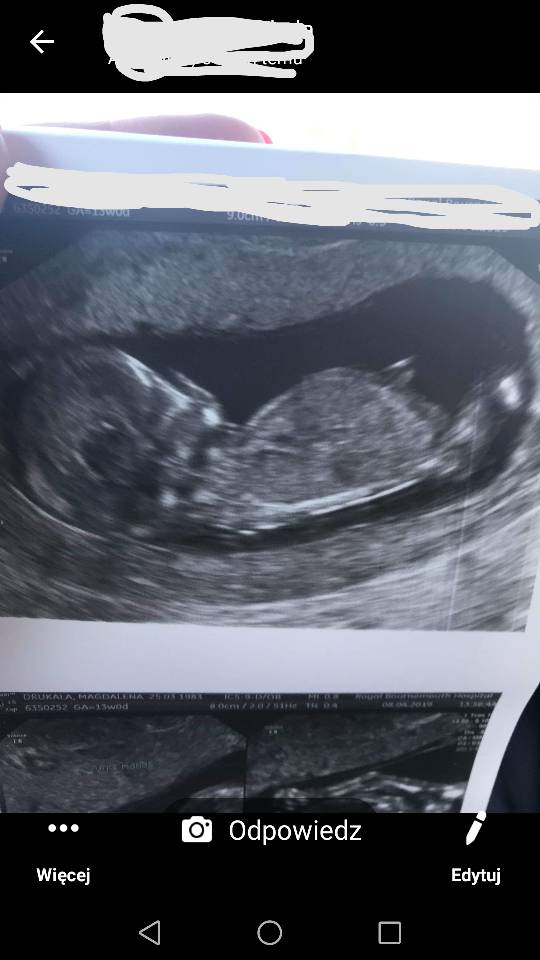

Usg chłopak czy dziewczynka

Witam w 19 tygodniu ciąży dowiedziałam się ze będę miała dziewczynkę w 20 tyg okazało się jednak , że to chłopak. Sama już nie wiem bo na jednym usg widać na pewno dziewuche a na drugim chłopca. Może to pempowina ?? Może ktoś mi pomoże rozwiązać ta zagadkę

• 4A8F5FF1-76CA-4DE0-AC12-5EDF08E820F2.jpg

4A8F5FF1-76CA-4DE0-AC12-5EDF08E820F2.jpg

596,4 KB · Wyświetleń: 23 779